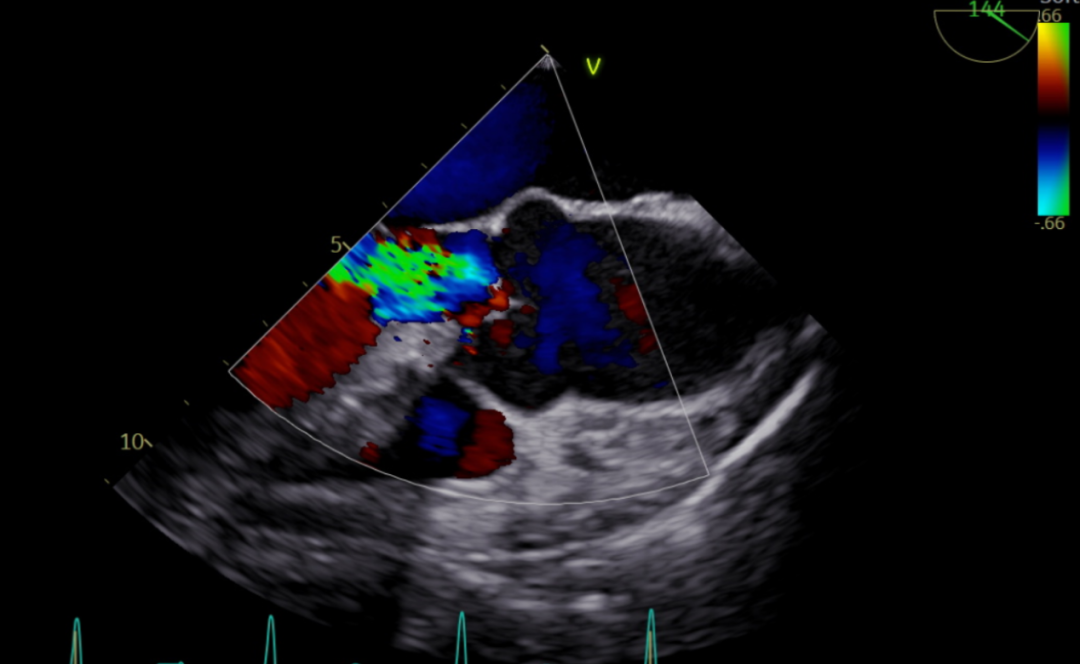

术前超声影像图